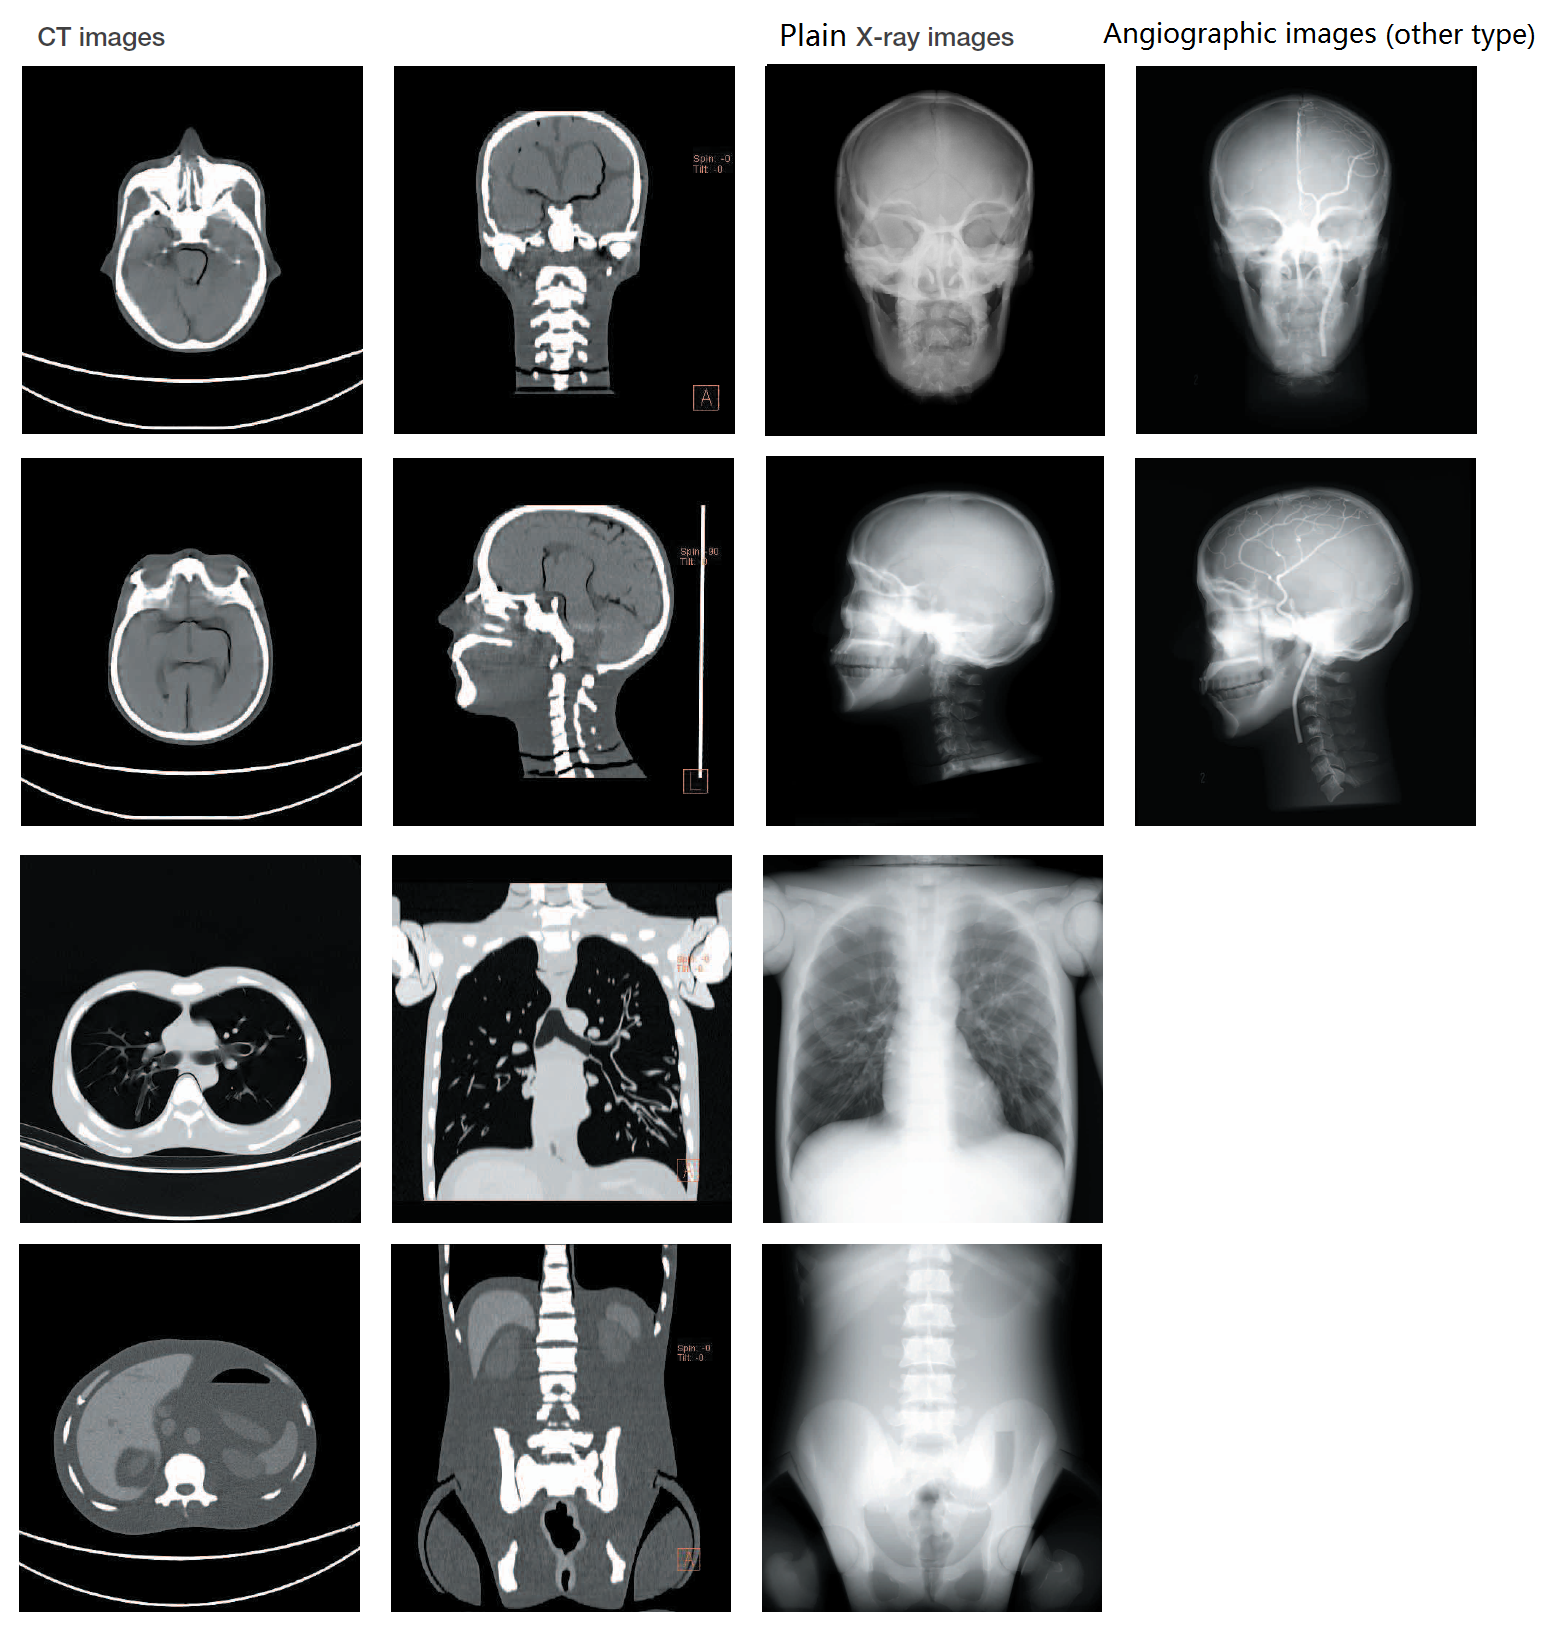

模型1:1 真人等比例大小,無(wú)論是骨骼還是內(nèi)臟器官都擁有與人體相同的X 線吸收率。在普放設(shè)備與CT 下都能得到與真人高度相似的透視圖像,并且支持3D 影像重建??蓜?dòng)式關(guān)節(jié)設(shè)計(jì),允許按照臨床實(shí)際擺放拍攝體位,且各個(gè)部位都可快速的分解拆卸,單獨(dú)使用??捎糜谟跋窠虒W(xué),訓(xùn)練技師,圖像質(zhì)量管理,設(shè)備研發(fā)等多種用途。領(lǐng)先材料,不含任何有害物質(zhì)以及金屬材料。

材料:特質(zhì)聚氨酯

成人男子全身大小,長(zhǎng)約165cm,重量50kg

可分解數(shù):10部分

·精確的解剖學(xué)結(jié)構(gòu)。真人比例大小。

·全身可動(dòng)設(shè)計(jì),各關(guān)節(jié)均可拆卸。

·與人體各組織相一致的X 線吸收率。

·全身都可獲得平片,CT,以及3D 重建影像。

·各個(gè)內(nèi)臟組織以及骨骼都可以進(jìn)行病例定制,如骨折,肝癌,膽結(jié)石等。

·不含有害物質(zhì)和金屬。

·可獲取的圖像

頭部:·頭骨 ·頸椎骨 ·腦 ·大腦 ·中腦 ·小腦 ·腦室 ·眼球 ·動(dòng)脈(僅左半部帶造影劑)

軀干:·脊椎骨 ·鎖骨 ·肋骨 ·胸骨 ·肩胛骨 ·髖骨 ·大腿骨 ·肺(肺血管)·氣管 ·心臟 ·肝臟和肝靜脈 ·胰臟 ·腎臟 ·膽囊 ·脾臟 ·精囊 ·大動(dòng)脈·大靜脈 ·尿管 ·膀胱 ·前列腺 ·直腸 ·乙狀結(jié)腸

可用于普放設(shè)備拍攝,也可用于CT建模。

適用于普通X射線平片拍攝,CT計(jì)算機(jī)斷層掃描裝置,及三維圖象重建用途的多功能影像模型,可用于各式讀片訓(xùn)練和解剖教學(xué)、設(shè)備例行檢測(cè)及校對(duì)和日常影像質(zhì)量評(píng)估。